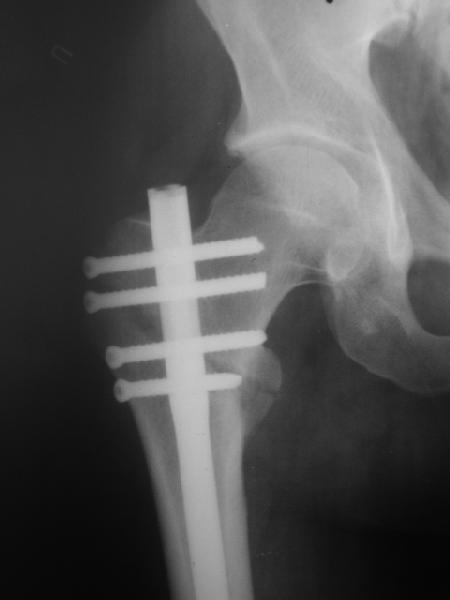

При межвертельных переломах с цефаломедуллярными гвоздями бывает, что проксимальый винт проходит или черед периферический отломок, или прямо над ним. И если остался диастаз, то этот винт при осевой нагрузке не дает сблизиться отломкам. Пример такого остеосинтеза в застарелом случае в приложении.

В качестве предупреждающей меры можно долотом разрушить латеральную стенку дистального отломка под винтом.

В частности, на проксимальном конце сделано еще одно дополнительное статическое отверстие. Можно ввести в проксимальном отделе 4 винта, из них 3 статические (2 в круглые отверстия и 1 по нижнему краю овального). Картинки в приложении. На дистальном конце стержня тоже кое-что улучшено. Спрашивайте в аптеках, как говорится. Выпускается предприятием "ЦИТО" (Москва), то есть это малобюджетное решение.

Конечно, мы не синтезируем остеопорозые вертельные переломы согласно прилагаемому примеру, винты 6 мм вырежутся. Но у более молодых при хорошем качестве кости такие или подобные гвозди с поперечным расположением винтов вполне применимы для меж- и подвертельных переломов.

Женя, эта картинка показывает не оптимальное лечение вертельных переломов в моем представлении, а особенности дизайна упомяутого фиксатора.

В частности, его возможности при фиксации переломов проксимального отдела бедра - в сравнении с другими, имеюшими лишь по одному статическому и динамическому отверстию и с кондуктором для введения 2 винтов.

Это было года 2,5 назад, мы тогда еще уточняли возможности шинирования с угловой стабильностью гвоздем с поперечным расположением винтов при переломах проксимального отдела бедра. Пациенту не пришлось приобретать намного более дорогой рекон или проксимальный гвоздь. В приложении еще несколько примеров применения того гвоздя при высоких переломах бедра, в том числе с более латеральной точкой входа. Гвоздь изгибаем для этого.